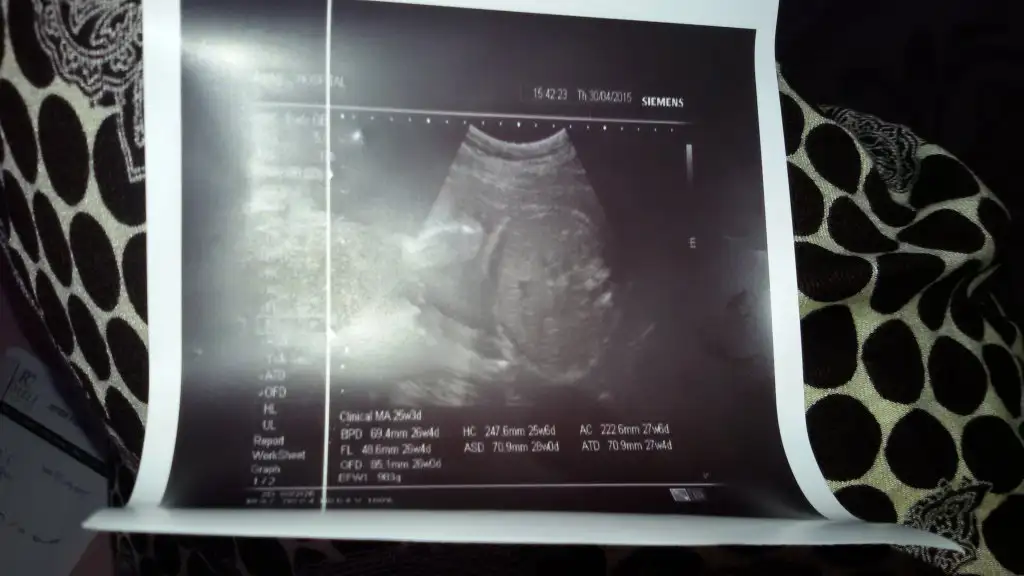

ben 25+5 te gittiğimde 980 gr dedi ama hiç iri bebek falan demedi gelişimi gayet iyi dedi sadeceSelam kizlar yarim saat once ultrasona girdim bebegim normalde 25+4 tu bugun.

Ama 26+4 1 hafta onden geliyor ve 983gr doktor cok iri bebek dedi boyle giderse normal dogum imkansiz dedi cok sukur saglikli kizim kipir kipir ama uzuldum boyle deyince hatta 4 kilo ve ustu de cikabilir dedi.

fotodaki olculerimiz :/ resim gobisi ve ayaklari var.